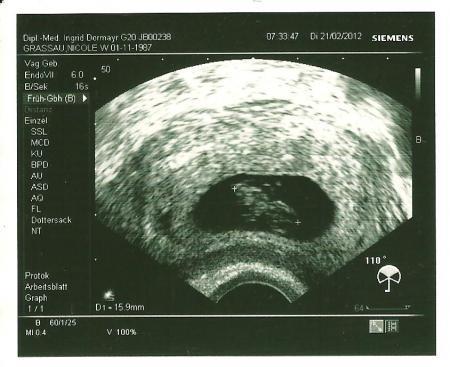

Hallo also zurück von meinem termin heute gabe denn Mutterpass und ab morgen darf ich nur noch 5 Stunden arbeiten aber es war alles in ordung das kleine ist schön gewaschen 1,6 cm für 8+3 ist völlig okay meinte meine Ärztin nun muss ich wieder warten bis zum 14.03 das ich denn kleinen Wurm wieder sehen darf! Aber es ist schon toll das so kleine dinge einen so sprachlos machen können! Ich bin so Glücklich!

Bild zu